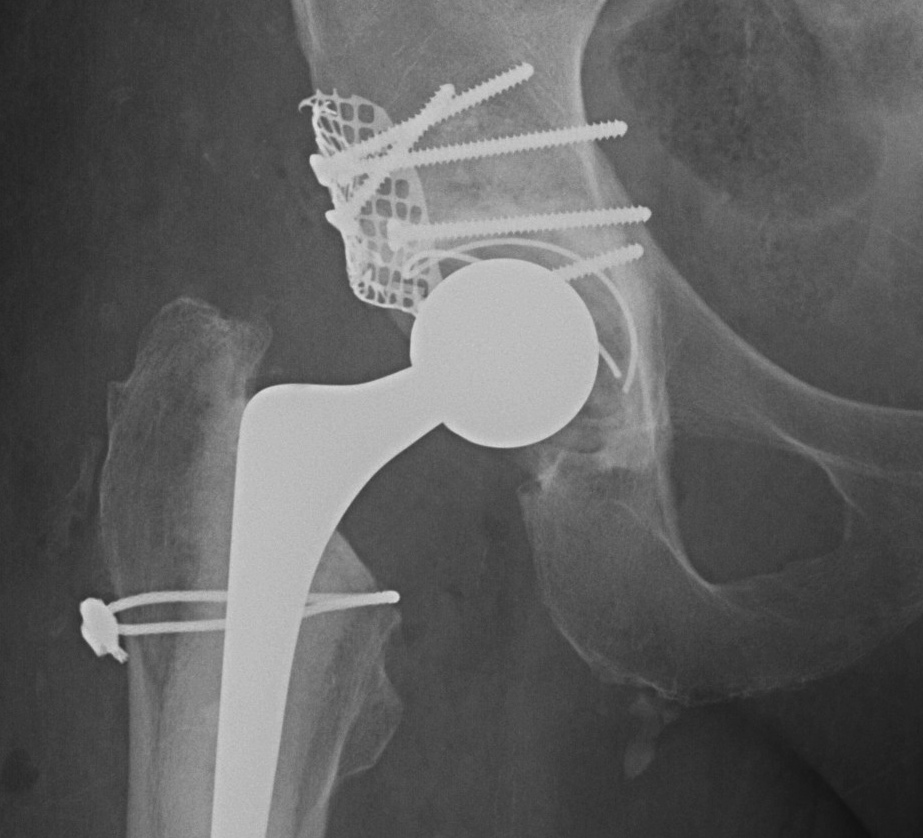

Type IIIC

- < 50% rim intact, < 40% contact

- must reconstruct for stability

- unable to use uncemented component

- use bone graft to reconstruct

- need cage for stability

1. Structural Allograft + Cage

Indications

- when inadequate bone stock precludes the use of uncemented acetabular components

Theory

- cannot implant onto allograft

- graft under the cage

- secure with cage

- cement poly into it

Technique

- allograft reconstruction of rim with femoral head

- allograft particulate material in base

- secure cage to posterior column ilium and ischium

- 3 screws in each

- cement all poly cup into cage

Results

- 75% 10 – 15 year survival

Option: Custom-made triflange components

CT guided model of pelvis

- custom made acetabular cage

- fits defect exactly

- flanges perfectly designed and not malleable to improve strength

- HA coated

- cement poly cup into it

- massive defects

- 90% 4.5 year survival in complicated patients

2. Impaction Bone Graft +/- Mesh + Cage + Cemented cup

Pelvic discontinuity

1. Plate and bone graft posterior column

2. Plate + Cage reconstruction

3. Cup Cage Reconstruction

- large tantalam cup inserted for reconstitution of discontinuity

- bone graft inserted

- cage, cement in cup